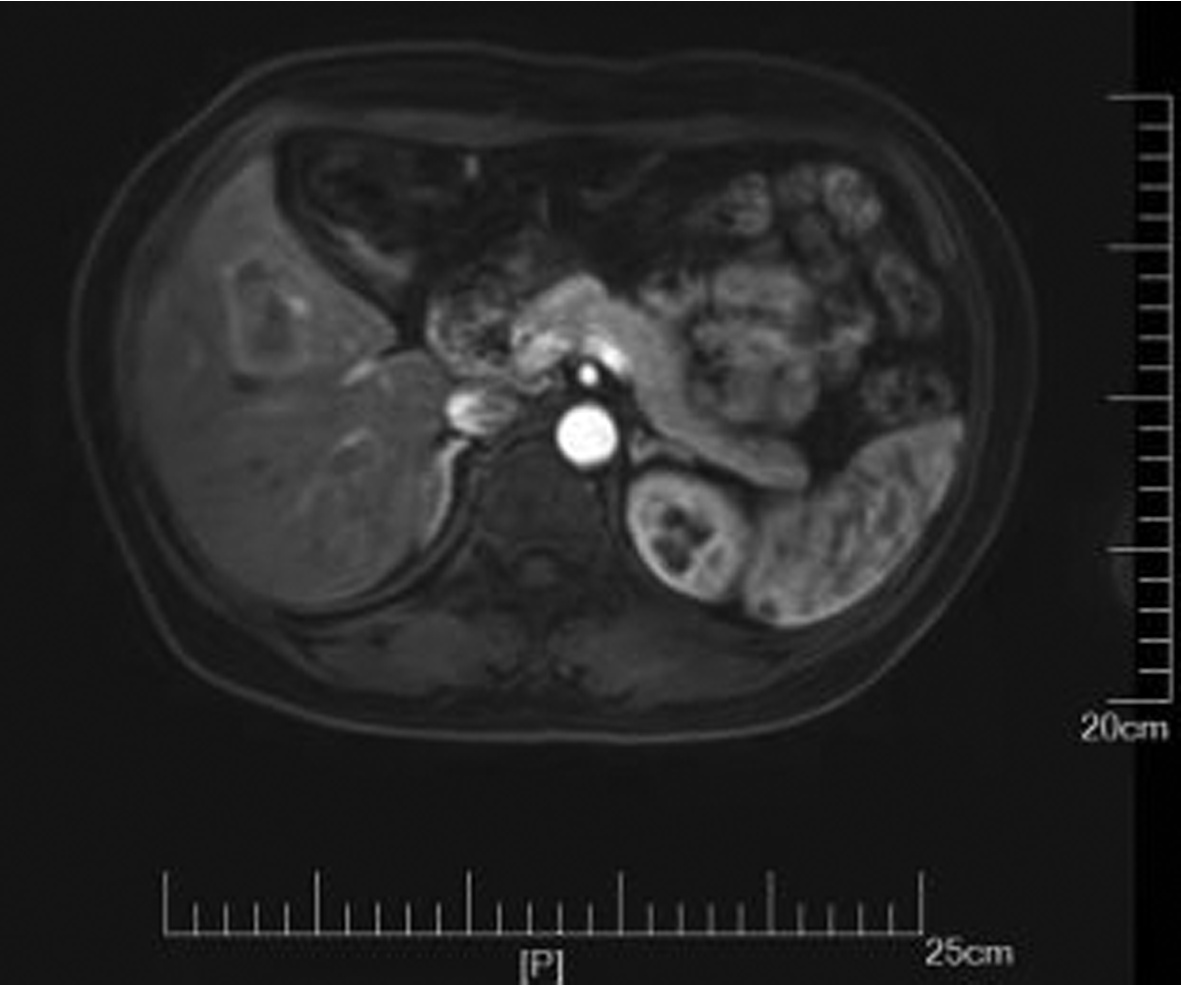

IgG4相关腹膜后纤维化1例报告

李朝霞, 刘洋, 李楠, 纪竹慧, 辛桂杰

2022, 38(5): 1126-1128. DOI: 10.3969/j.issn.1001-5256.2022.05.030

摘要(876) HTML (399) PDF (2161KB)(74)

摘要: